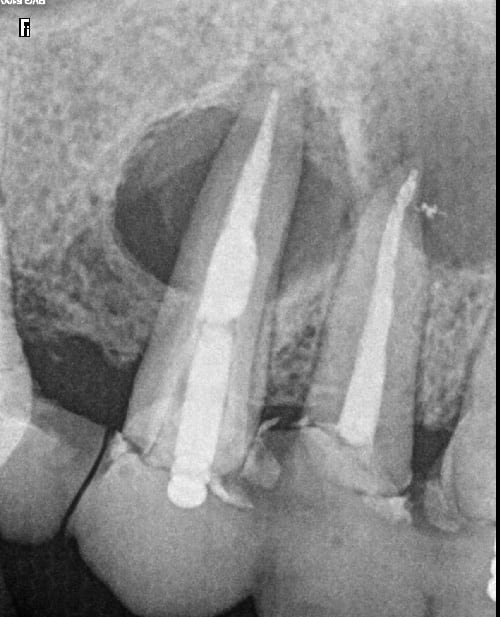

Quelques radios d'un cas en cours de traitement.

Aucun signe d'infection, pas de voussure, sauf une fistule en distal de la 13 qui apparaitrait régulièrement.

A votre avis la 12 peut elle être a l'origine des 2 lésions.

Si c'est le cas, l'extraction de la 12 pourait elle permettre de sauver la 13.

Qui est pour tout extraire (11 12 13)?

Une scanner pourrait-il être utile pour tenter d'en sauver une, afin de détemriner l'origine de la lésion ?